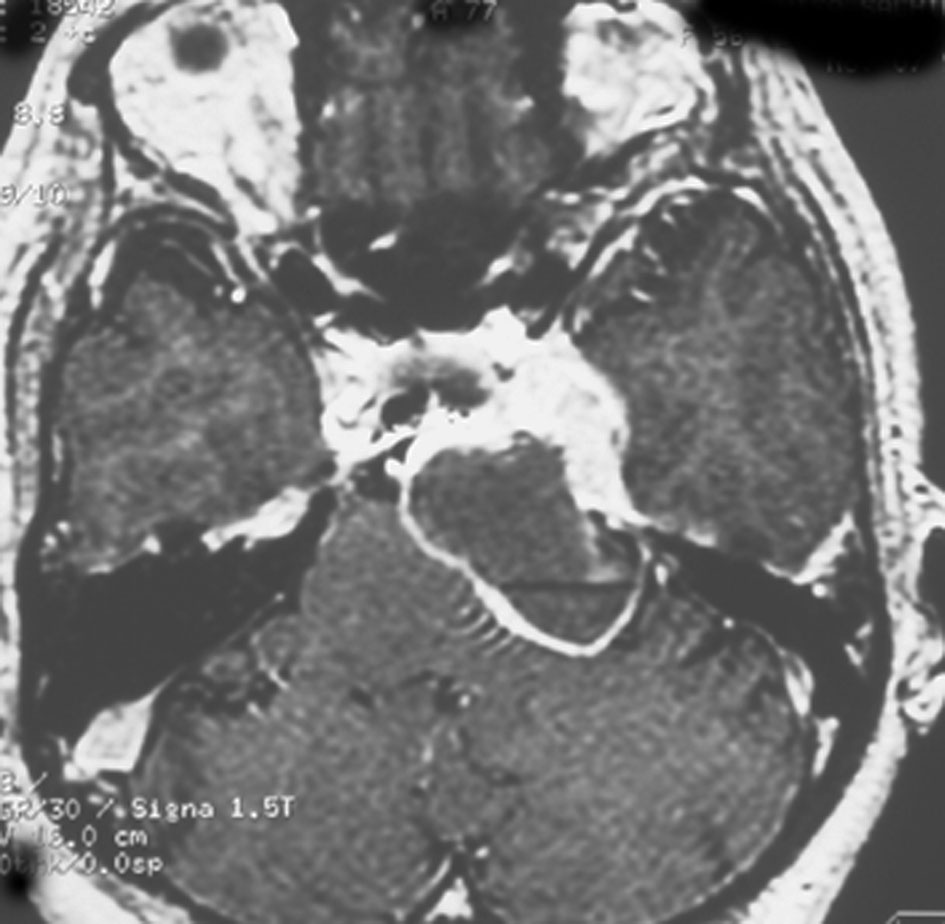

メッケル腔(ガッセル神経節)という場所から発生した三叉神経鞘腫のMRIです。サイズは放射線治療するには大きすぎます。ですから手術摘出します。手術には側頭開頭硬膜外法と経鼻内視鏡手術があります。内視鏡手術は三叉神経が外側に来ているので優位性があります。開頭手術では,側頭部の前の方を小さく開頭して脳の硬膜の外から腫瘍を見るだけで取れます。もちろん脳の損傷は起こさないようにしなければなりません。手術中には三叉神経が薄く広がって腫瘍のまわりにくっついていますからそれを大事に守りながら腫瘍を取っていきます。

手術のすぐ後のMRIです。幸いなことにこの患者さんでは,腫瘍を全部取ったのですが三叉神経の大部分を残すことができて,顔のしびれはとても軽くてすみました。全摘出すると経鼻手術でも開頭手術でも多少の顔面の痺れ(感覚低下)はでますが,日常生活に支障のないレベルに留めなければなりません。